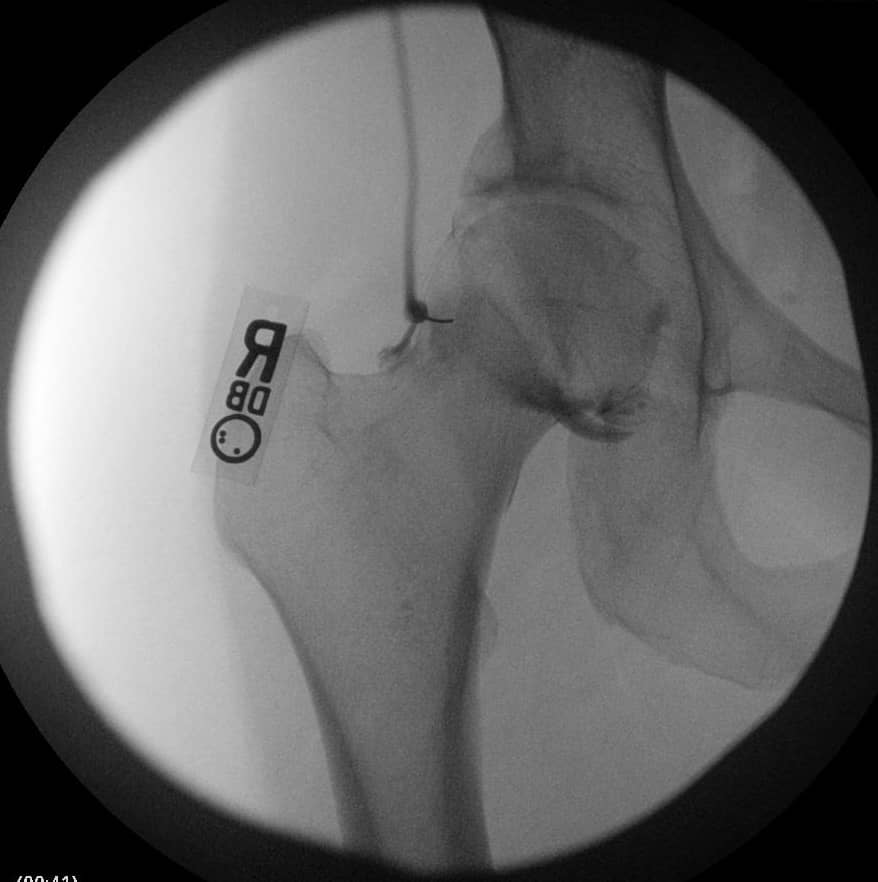

एक एपी श्रोणि दृश्य प्रभावित और अप्रभावित फेमोरा की तुलना की अनुमति देता है। यह सुनिश्चित करने के लिए समरूपता का आकलन करें कि एक सच्चा एपी दृश्य कैप्चर किया गया है। इसका आकलन यह जांचकर किया जा सकता है कि कोक्सीक्स सिम्फिसिस पबिस को ओवरलैप करता है, जिसमें दो संरचनाओं के बीच 2 सेमी से अधिक अलगाव नहीं होता है। संयुक्त स्थान में कमी और अपक्षयी परिवर्तनों के लिए संयुक्त का मूल्यांकन किया जाना चाहिए। अप्रभावित पक्ष के साथ एंटेरोलेटरल गर्दन समोच्च की तुलना करें। बेहतर गर्दन की शंकु की कमी सिर-गर्दन ऑफसेट को कम करने का संकेत देती है। एंटेरोसुपीरियर या पूर्ववर्ती सिर की सपाट या बढ़ी हुई त्रिज्या एक गोलाकार सिर को इंगित करती है। कई मापों का विश्लेषण किया जा सकता है:

- एफएआई के मूल्यांकन के लिए एक क्रॉस-टेबल पार्श्व दृश्य महत्वपूर्ण है, जिससे एंटेरोलेटरल फेमोरल गर्दन का दृश्य देखने की अनुमति मिलती है।

- अल्फा-कोण: ऊरु गर्दन की मध्य रेखा के साथ एक रेखा और ऊरु सिर के केंद्र से उस बिंदु तक एक रेखा के बीच बनता है जहां अतिरिक्त हड्डी सामान्य ऊरु सिर स्फेरिसिटी से विचलित होती है। 60 डिग्री से अधिक का कोण एफएआई को इंगित करता है।

- सिर-गर्दन ऑफसेट: ऊरु गर्दन के अनुदैर्ध्य अक्ष को विभाजित करने वाली रेखा से शुरू करें। एक समानांतर रेखा खींचें जो ऊरु गर्दन के पूर्ववर्ती पहलू के लिए स्पर्शरेखीय है और पूर्ववर्ती ऊरु सिर के समानांतर रेखा स्पर्शरेखा की दूरी को मापें। सामान्य दूरी 9 मिमी से अधिक है या सिर के व्यास का अनुपात 0.17 से अधिक है।

एफएआई या तो कैम के टकराव, तथाकथित "पिस्तौल पकड़ विकृति" या पिंसर के अतिक्रमण के कारण होता है, जो अतिरिक्त एसिटेबुलर कवरेज के कारण होता है। कैम इम्पैक्टमेंट के एटियलजि स्पष्ट नहीं है, लेकिन ऊरु गर्दन ऑफसेट में कमी से कूल्हे में दर्द हो सकता है और अंततः समय के साथ लैब्रल आँसू और चोंड्रल क्षति हो सकती है। घटी हुई ऊरु सिर-से-गर्दन व्यास अनुपात ऊरु गर्दन को गहरे कूल्हे के फ्लेक्सन में पूर्ववर्ती एसिटाबुलम और लैब्रम पर घूमने की अनुमति देता है। पुरानी, दोहराए जाने वाले आघात से मामूली या पूरी तरह से अनुपस्थित आघात की उपस्थिति में गठिया परिवर्तन या लैब्रल आँसू हो सकते हैं। 6